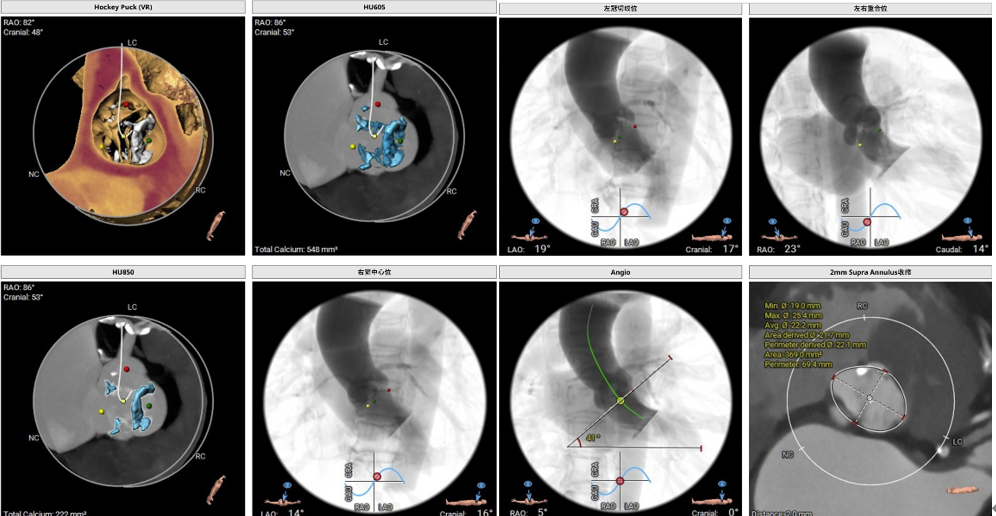

二.TAVR术前CT评估(图3-5):

Type1(LN)型二叶式主动脉瓣,瓣叶轻度钙化并增厚,钙化分布不均匀;双侧冠脉开口高度可;瓦氏窦可、窦管交界可、升主动脉可、左室心腔内径可;主动脉瓣环水平夹角41°;双侧髂股走形可, 双侧髂股动脉内径可。全面评估后决定在导管室、局麻下行极简式TAVR。

(图3)

(图4)

(图5)